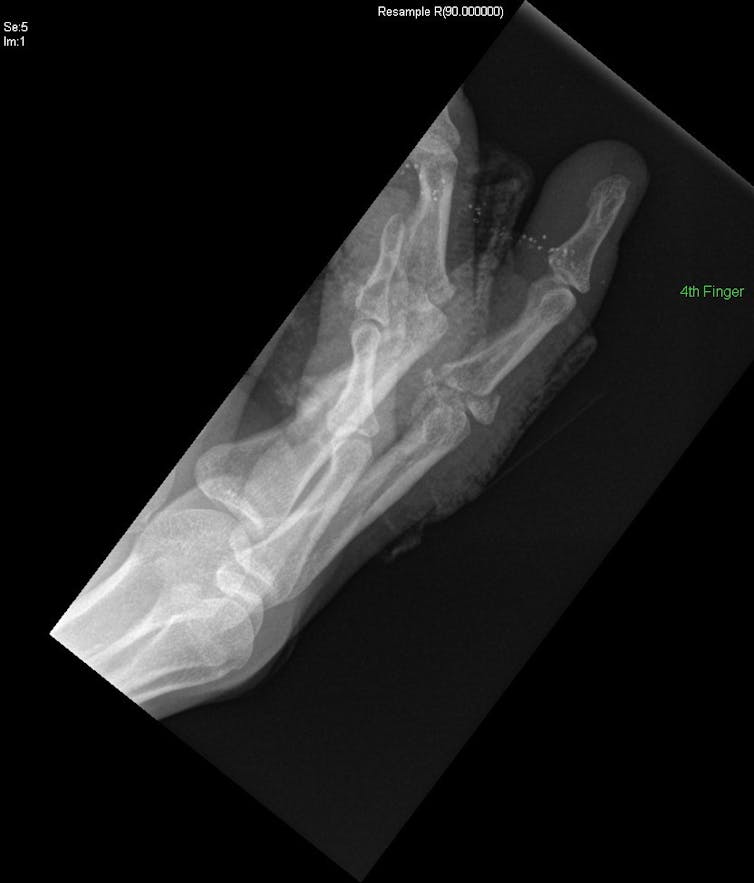

The most common injuries were finger dislocations, with or without fractures, to the proximal interphalangeal joint (the middle joint on the x-ray shown) of the little and ring fingers. Next came metacarpal fractures (in the bone below the knuckles).